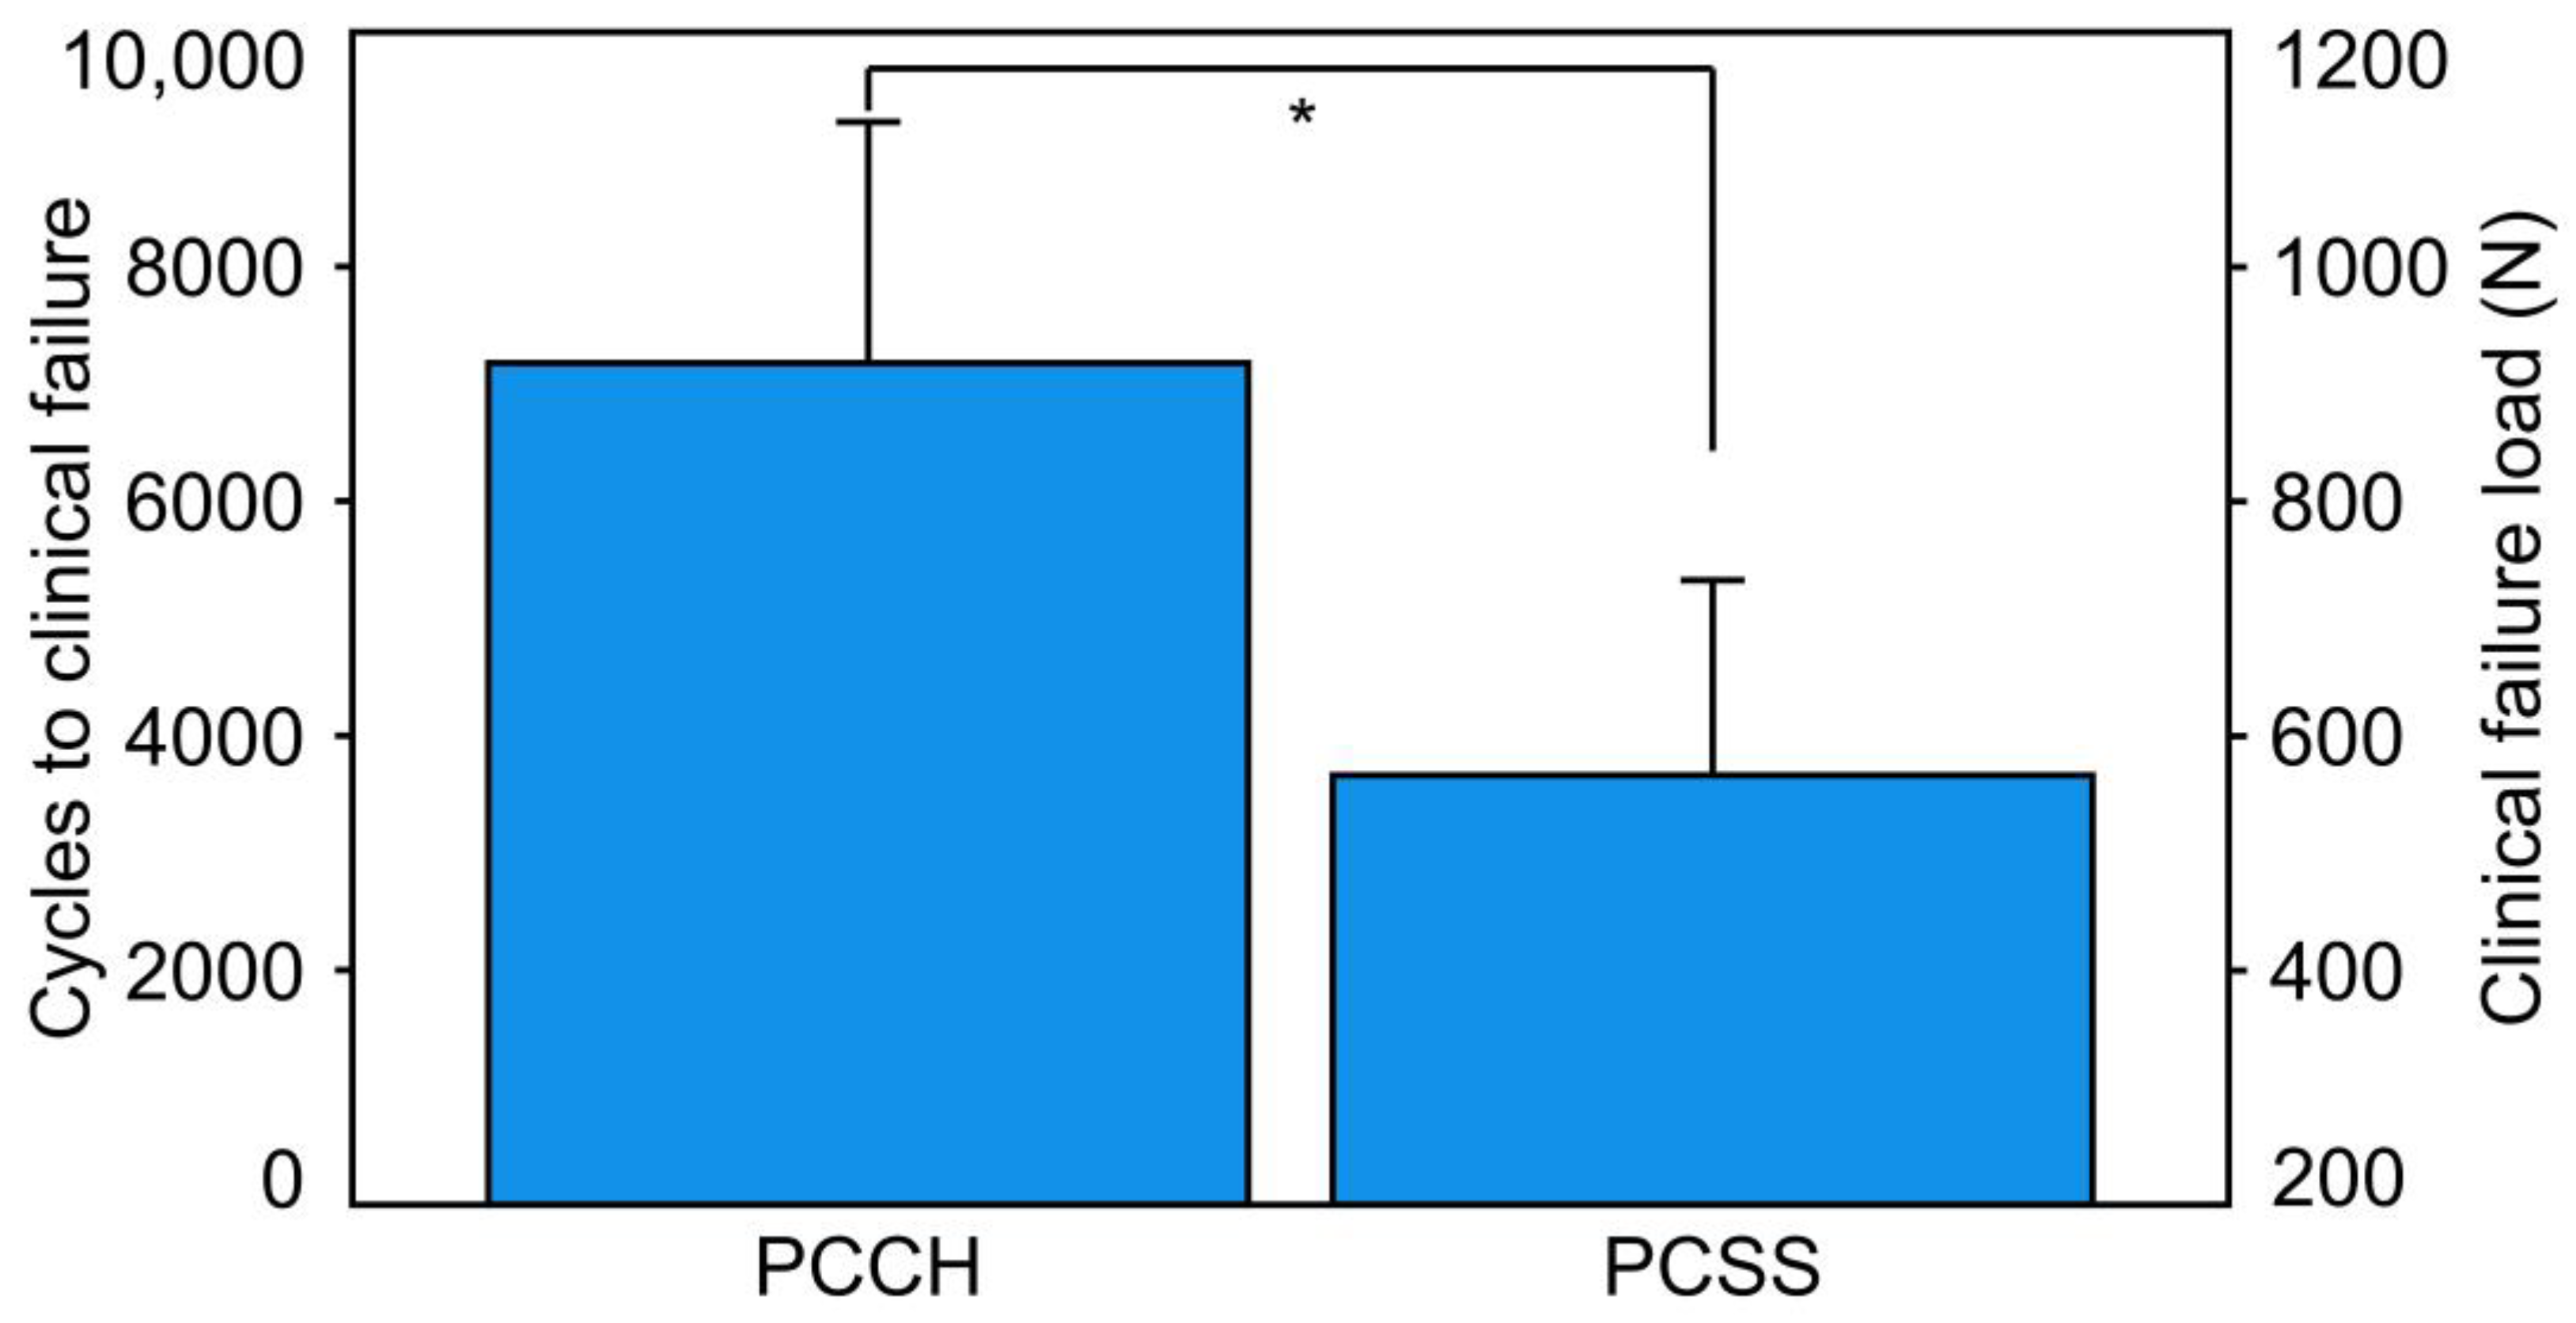

3. Results

- Cycles to clinical failure and clinical failure load were significantly higher for PCCH versus PCSS.